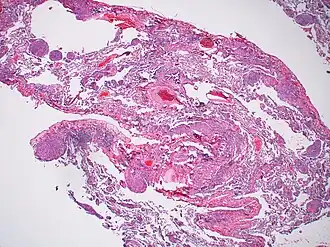

Лимфангиолейомиомато́з (ЛАМ) — редко встречающееся полисистемное заболевание, характеризующееся прогрессирующей кистозной деструкцией лёгочной ткани, поражением лимфатической системы и появлением опухолевидных образований (ангиомиолипом) органов брюшной полости. Заболевание поражает в основном женщин репродуктивного возраста и проявляется спонтанными пневмотораксами, прогрессирующей одышкой при физической нагрузке, хилотораксами и редкими эпизодами кровохарканья. Лимфангиолейомиоматоз может развиваться без явной причины или же в рамках наследственного заболевания — туберозного склероза[2][3].